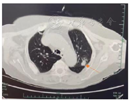

影像学检查:甲状旁腺超声:右侧甲状旁腺区见数枚低回声结节(较大者29 mm×18 mm),边界清晰,形态规则,内见条状血流信号(图1);左侧甲状旁腺区见数枚低回声结节(较大者37 mm×25 mm),边界清晰,形态规则,内见条状血流信号。甲状旁腺ECT示右侧甲状旁腺高功能腺瘤(图2)。肾上腺超声:左侧肾上腺见35 mm×29 mm低回声包块,边界清,形态规则,内部回声不规则,MR鞍区和垂体平扫示垂体瘤术后改变。髂关节正侧位片:双侧髂关节骨质疏松,骨密度;骨质疏松。胸部CT:两侧胸廓组成骨多发骨质改变,伴部分病理性骨折考虑,双肾结石,左肾萎缩、积水,左侧肾上腺肿块,胰头前方、胰头钩突下方见圆形低密度影。

术后第2天测血钙正常,全段甲状旁腺激素低于正常值下限,血气出现明显代谢性酸中毒,予碳酸氢钠纠酸处理,后10 d多次测血钙降低,最低血钙1.45 mmol/L,予钙尔奇D口服补钙、葡萄糖酸钙针静脉补钙,术后第13天复测血钙恢复正常。当时出院诊断"慢性肾衰竭、软组织感染、多发性内分泌除瘤病、甲状旁腺肿瘤术后、高钙血症、高磷血症、低钙血症、低镁血症、骨质疏松、甲状腺结节、肾上腺肿物、垂体瘤手术个人史、高泌乳素血症、低蛋白血症、泌尿道感染、低钾血症、低钠血症、高尿酸血症、胃炎、双侧肾结石、胆囊肿大、胆囊结石、单纯性肾囊肿、肺部阴影(两肺小结节)"等。